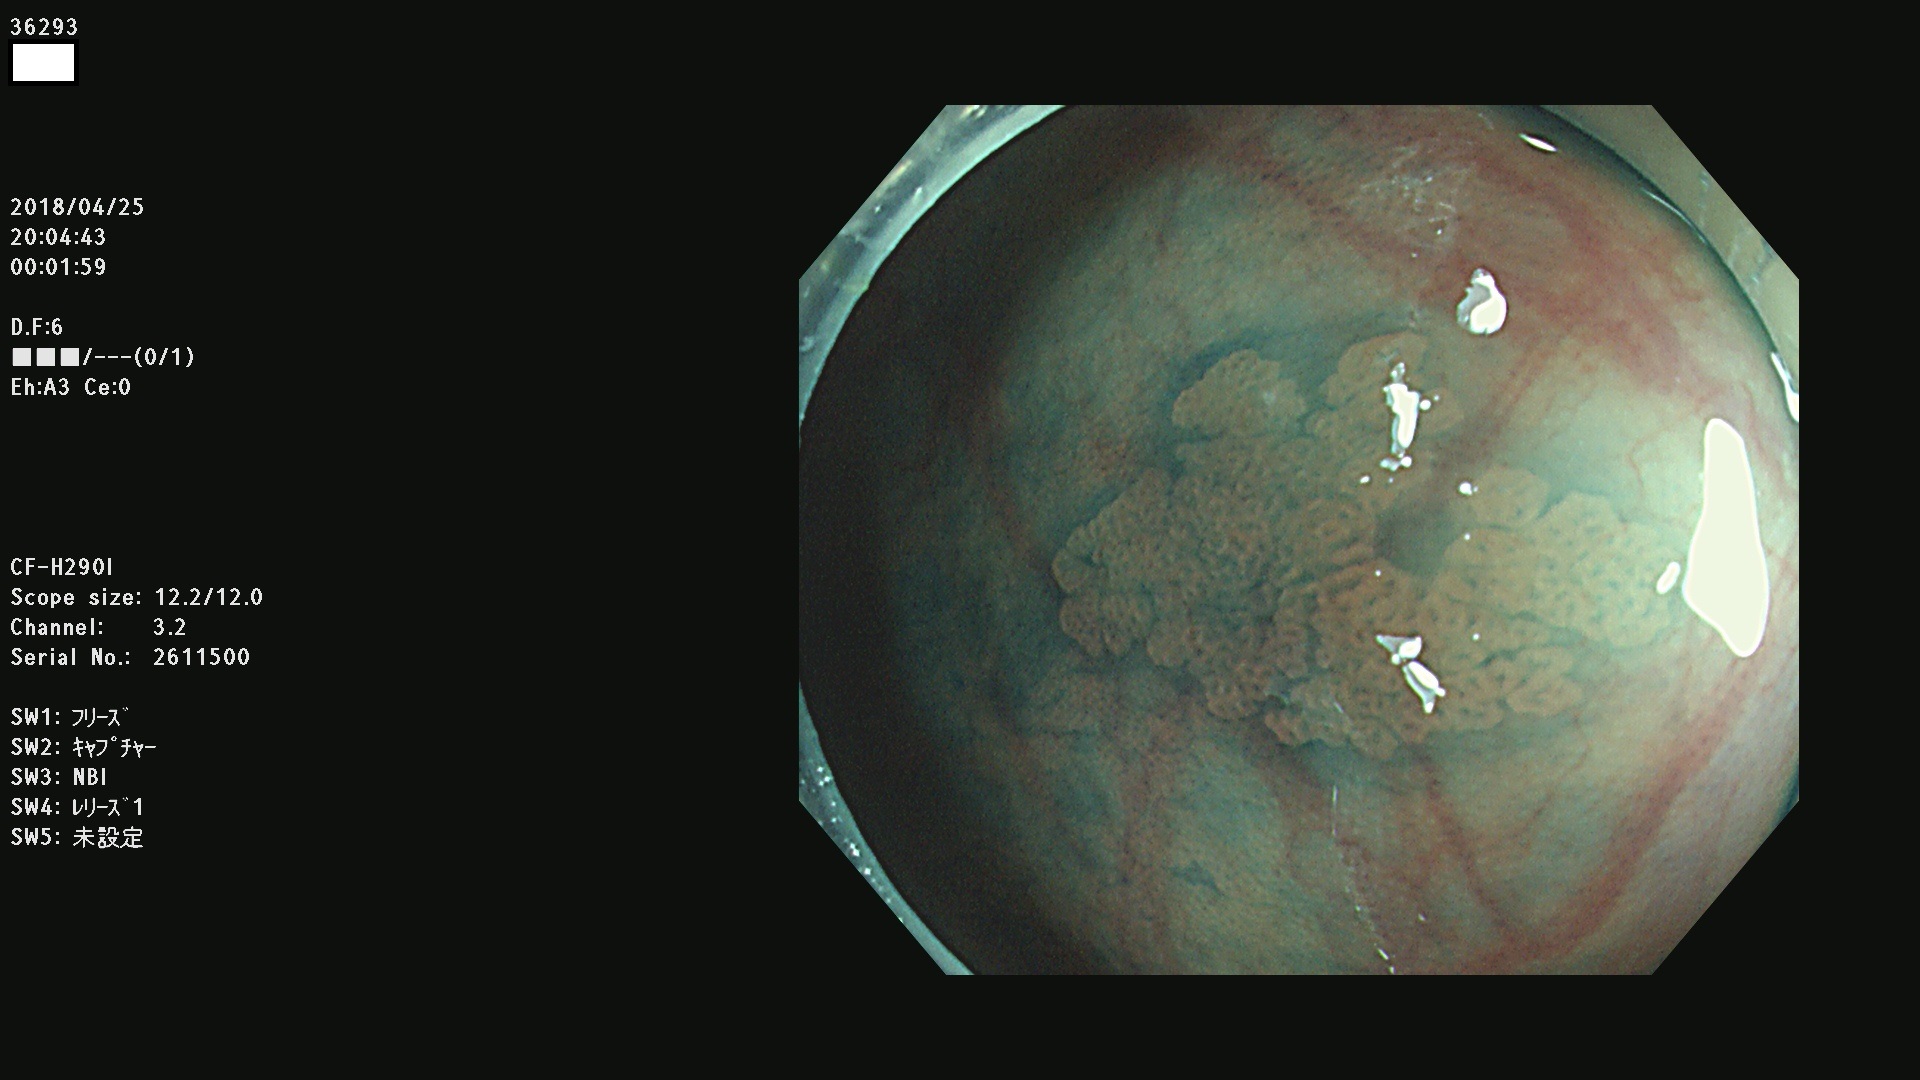

発見困難で危険性の高い平坦型病変(上記100名より抽出)